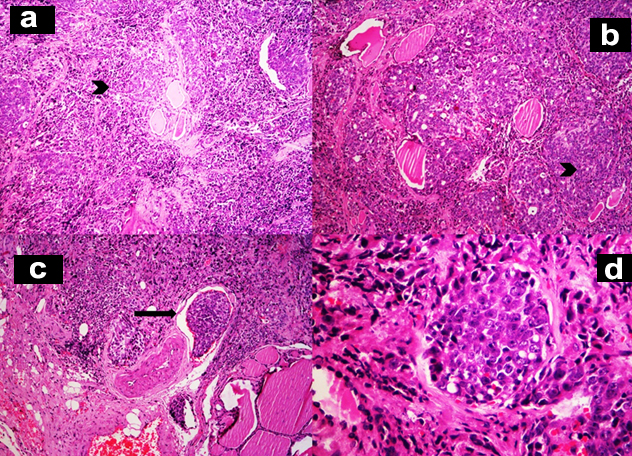

Grossly, the thyroid gland was mildly enlarged with right lobe measuring 6.5x3.5x1.5 cm and left lobe measuring 5.5x2x1.5 cm. Serial sections through the left lobe revealed a single, ill defined, grey white, firm lesion measuring 1.3x1x0.9 cm [Table/Fig-2]. Histopathological examination of this lesion revealed thyroid parenchyma with interstitial infiltrates of a malignant neoplasm composed of round to oval cells exhibiting high nucleocytoplasmic ratio, vesicular nuclei and prominent 1-2 nucleoli arranged in sheets, nests, vague glandular pattern, cords and singly. Multiple lymphatic emboli were noted [Table/Fig-3]. Immunohistochemistry (IHC) was performed. These atypical cells were positive for cytokeratin (CK), PSA and Prostatic Specific Acid Phosphatase (PSAP). Thyroid Transcription factor-1 (TTF-1) was negative [Table/Fig-4]. The final diagnosis was metastatic prostatic adenocarcinoma to the left lobe of thyroid gland.

a,b-Interstitium of thyroid gland is infiltrated by sheets and nests of atypical cells (H&E,x100); c-Lymphatic emboli are evident (H&E,x100); d-These atypical cells have high nucleocytoplasmic ratio, vesicular nuclei and prominent nucleoli (H&E,x400);